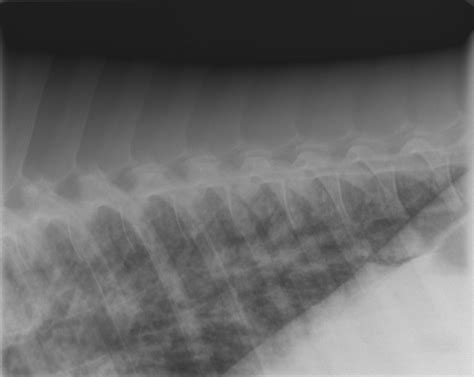

• Radiographs (X-rays): Chest X-rays can reveal inflammation, fluid, or other abnormalities in the lungs.